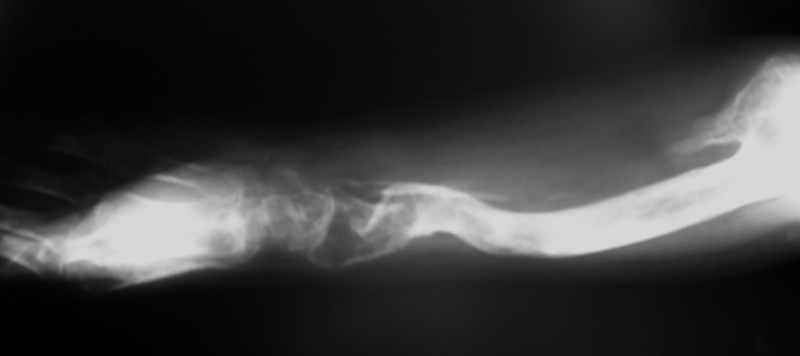

Ещё одно клиническое наблюдение - лимфома кости, до и после ПХТ и лучевой терапии.